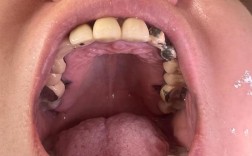

充填治疗(补牙):

(图片来源网络,侵删)- 适用情况: 最常见的蛀牙(龋齿)、牙齿小面积缺损(如楔状缺损)、轻微的牙体组织磨损。

- 方法: 去除腐坏或受损的牙体组织,用修复材料(如复合树脂、玻璃离子水门汀、银汞合金等)恢复牙齿的外形和功能。